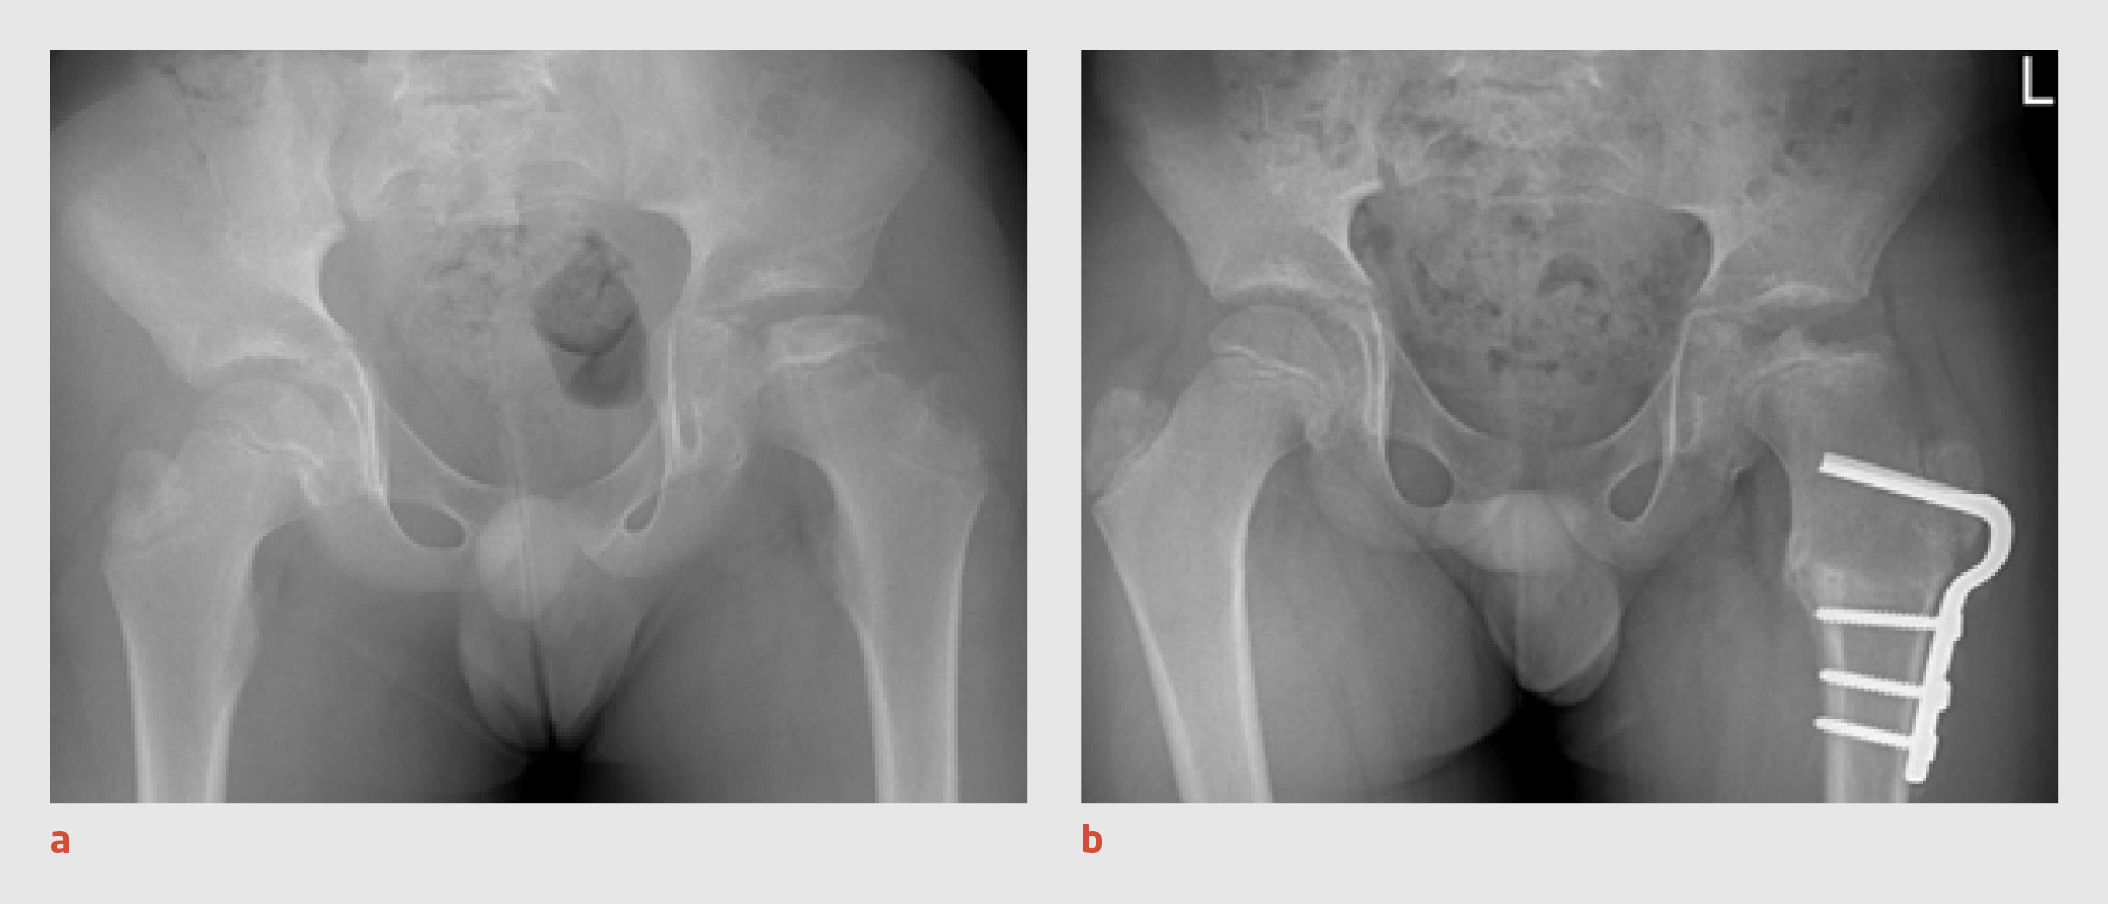

Patiënt C, een 8-jarige jongen, werd door de huisarts verwezen naar de polikliniek Orthopedie vanwege pijn in de linker lies die sinds 4 weken bestond. Bij lichamelijk onderzoek op de polikliniek zagen wij een kind dat mank liep en zijn linker heup in flexiestand hield. Het functieonderzoek van de linker heup toonde een flexiecontractuur van 10°, een beperkte exorotatie tot 30° en een beperkte endorotatie tot 20°. Aan de rechter zijde was exorotatie mogelijk tot 70° en endorotatie tot 50°. De röntgenopname van het bekken liet een afplatting van de epifyse van de linker heup zien, die past bij de ziekte van Perthes (figuur 2).

Figuur 2

De ziekte van Perthes bij een 8-jarige jongen

Figuur 2 | De ziekte van Perthes bij een 8-jarige jongen

Röntgenopname van het bekken, waarop een afplatting van de epifyse van de linker heup te zien is, passend bij de ziekte van Perthes, Herring-type B.

Wij adviseerden om de heup te ontlasten. In de daaropvolgende maanden verslechterde echter zowel het klinisch als het radiologisch beeld, met een verdere afplatting en sclerose van het caput ossis femoris (figuur 3). Op het preoperatieve artrogram werd een ‘hinge abduction’ gezien – een gevolg van de ziekte van Perthes waarbij het craniolaterale deel van het caput ossis femoris uitsteekt buiten het acetabulum. Mede gezien de relatief late presentatie besloten wij een correctie-osteotomie van het proximale femur te verrichten om de positie van het femur ten opzichte van het acetabulum te verbeteren.